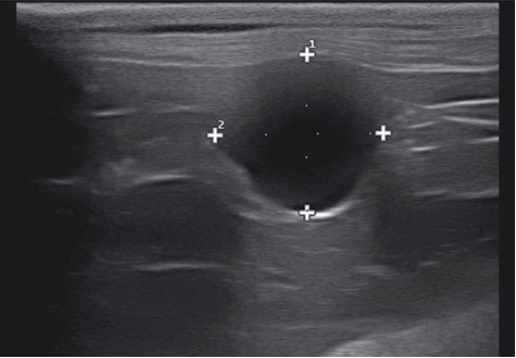

卵巢囊肿通常是超声检查时偶然发现的(非排卵性的卵泡囊肿),尤其发生在未生育的成年猫或老年母猫身上。卵泡囊肿是排卵失败所致,临床上需与卵巢旁囊肿、卵巢肿瘤等其他囊性病变进行鉴别。卵泡囊肿的超声影像表现为一个或多个直径约为1~5cm,界限清晰的无回声结构,囊壁高回声伴远场回声增强(图12)。该影像需与卵巢肿瘤进行鉴别,尤其是卵巢颗粒细胞瘤。只有组织病理学才能区分卵泡囊肿、卵巢旁囊肿以及卵巢肿瘤。